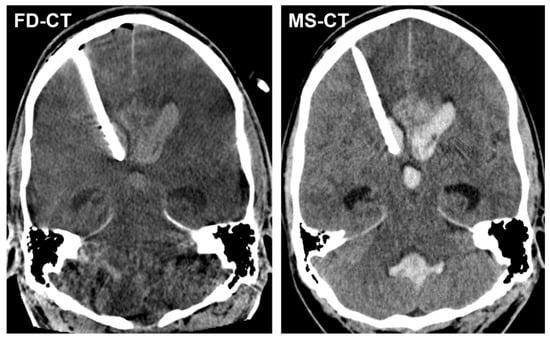

3.3.2. External Ventricular Drain Position

3.3.3. Acute Obstructive Hydrocephalus

3.4. Quantitative Analysis

3.4.2. Modified Graeb Score

4. Discussion